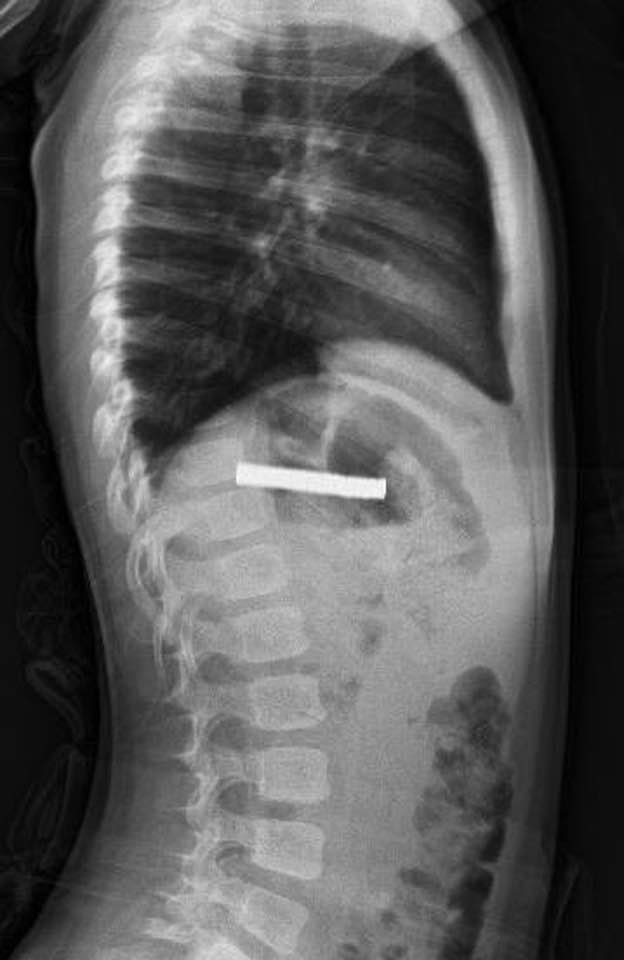

3 yaşındaki çocuğun yuttuğu ve yemek borusunu tıkayan 19 mıknatıs, Fırat Üniversitesi Hastanesi'nde yapılan başarılı bir operasyonla çıkarıldı.

Hastanede, FÜ Çocuk Gastroenteroloji Hepatoloji ve Beslenme Bilim Dalı Başkanı Prof. Dr. Yaşar Doğan tarafından yapılan tetkiklerde mıknatısların yapışarak çocuğun yemek borusunu tıkadığı tespit edildi.

Doğan ve ekibi tarafından yapılan müdahaleyle çocuğun yemek borusundaki mıknatıslar başarılı bir şekilde çıkarıldı.

Yapılan operasyon hakkında bilgi veren Doğan, "Tabi bu mıknatıslar uzun süre hastanın yemek borusunda kaldığı için biraz hasar bırakmıştı. Çok güçlü mıknatıslardı. İşlemin kolay yapılabilmesi için mıknatıslar yemek borusundan mideye alındı, mideden özel bir fileyle çıkarıldı. İşlemden sonra hastayı gece boyunca gözlem altında tuttuk. Sabah da aile kendi isteğiyle çıkarmak isteyince, hastanın da genel durumu iyi olduğundan taburcu ettik." dedi.